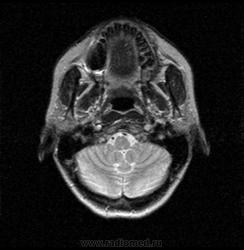

06.06.2011 МРТ - головы и шеи.

Пацентка 36 лет, с жалобами на припухлось в околоушной области справа.

В глубокой доле  правой околоушной железы  на фоне неизмененной паренхимы зона  гетерогенного по Т2, гипоинтенсивного по Т1  с единичными гиперинтенсивными включениями.При контрастировании- накопление контраста диффузное неоднородное и по периферии.Рискну предположить злокачественное образование ( аденокарцинома) с низкой степенью злокачественности( есть капсула, экспансивный рост).Сильно не расстреливайте.

Проблема в том, что перед челюстно-лицевым хирургом стоит распространенность любого объемного процесса, в данном случае все упирается в возмможную травму лицевого нерва и конечно же с дальнейшим его парезом, а ведь женщина  еще молодая. Образование имеет тонкостенную оболочку, по структуре неоднородно, с наличием кальцината, при этом МР-сигнал от окружающих анатомических структур(как костных так и мышечных) не изменен, т.е. об инфильтративном росте речи не идет, в какой то степени доброкачественное. В конкретном случае лицевой нерв с ретромандибулярной веной просто несколько оттеснен.

По гистологии аденома околоушной слюнной железы, но после удаления пока сохраняется парез лицевой мускулатуры, возможно временный.